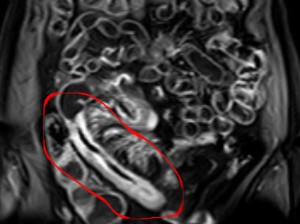

Crohn's disease is one of a number of inflammatory bowel diseases. Generally symptoms involve inflammation modulated abdominal pain, diarrhea, weight loss and malnutrition. The prevalence of the condition is higher in smokers and in those who overuse NSAID's and/or antibiotics, but this range of conditions is increasing generally with strong relations to diet and other environmental factors (related study).

Clinically, moxibustion has shown positive effects on any number of digestive and inflammatory related conditions. To look specifically at how this technique may influence Crohn's disease, a large team of researchers from the Shanghai University of Traditional Chinese Medicine recently conducted a study entitled "Herbs-partitioned moxibustion improves intestinal epithelial tight junctions by upregulating A20 expression in a mouse model of Crohn's disease". They were looking specifically at the mechanisms through which moxibustion may aid the backdrop of inflammatory functions involved with Crohn's disease.